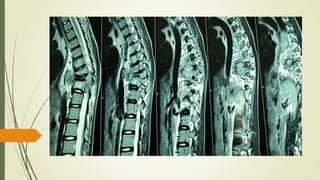

MRI Spine

• 37.